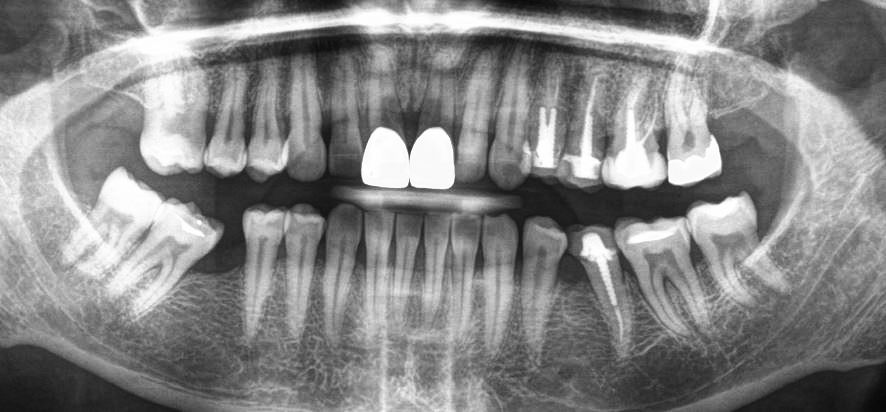

Hier sind die Zähne vollständig zu sehen, im Gegensatz zu den sog. Bite Wings, wo es nur darum geht, zu erkennen, ob Karies an den Zahnhälsen vorliegt.

In diesem Bild erkennen wir alles gesunde Zähne, die Wurzeln sind mit dem Kieferknochen verbunden. Die Weisheitszähne fehlen und es liegt ein Implantat im linken Unterkiefer vor (Betrachtung ist immer spiegelbildlich!) welches gut mit dem Knochen verheilt ist. Die Zähne sind somit kaum für Beschwerden verantwortlich. Eine weitere Abklärung drängt sich nicht auf.

Dies im Gegensatz zu diesem Patienten:

Es liegen hier viele wurzelbehandelte Zähne vor, welche zudem schlecht gemacht wurden, und entsprechend viele Hinweise auf gesundheitlich belastende Zustände.

Schlechte Wurzelbehandlungen sind auch erkennbar an den unregelmässigen Rändern welche die meisten der wurzelbehandelten Zähnen aufweisen (vergleichen Sie mit dem grünen guten wurzelbehandelten Zahn.).

Sollte so jemanden sich über chronische Entzündungen beschweren, so ist es Pflicht von jedem Arzt und Zahnarzt, solche potentielle Herde in den Überlegungen mit einzubeziehen.